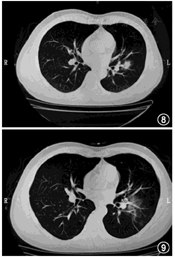

例3 患者男,37岁,有明确接触史。因反复发热,体温均低于38.5℃,伴胸闷、四肢乏力等不适,1月23日行胸部CT确诊为疑似病例(图8),1月25日晚开始服药,在基础方的基础上蒲公英增量至15 g,因药材原料缺乏问题,药材仅能使用3 d,1月29日药品服完,1月31日复诊,再次出现低烧。复诊CT见图9。因患者疗程不够,暂无法对疗效进行评估。